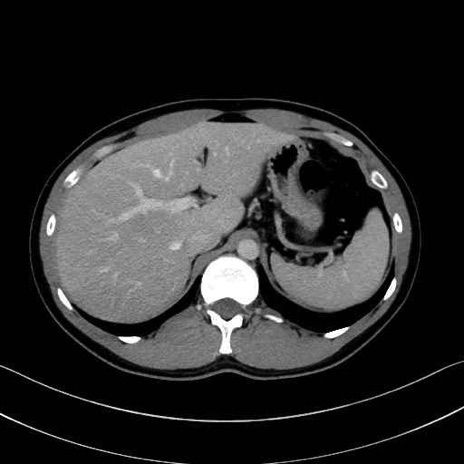

1. 体幹部(腹部・背部・後腹壁)の筋肉

腹直筋 (Rectus abdominis)

外腹斜筋 (External oblique)

内腹斜筋 (Internal oblique)

腹横筋 (Transversus abdominis)

腰方形筋 (Quadratus lumborum)

広背筋 (Latissimus dorsi)